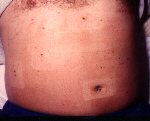

Es kann überhaupt keine Frage sein, daß ein deratig übergewichtiger Patient der am Tage Null noch so auf dem Operationstisch liegt wie auf dem linken Bild, und sich dann am Tage 2 nach der Operation bereits so wie auf dem rechten Bild fotografieren läßt, einen großen Benefit von der laparoskopischen Methode erhält.

adipoes.jpg (21581 Byte)  DICKNACHOP.jpg (17292 Byte) li: Operationstag, re: 2.Tag  nach  OP

Bedenken Sie die Komplikationsträchtigkeit eines solch adipösen (dickleibigen) Patienten, wenn Sie ihn laparotomieren (mit großem Bauchschnitt operieren) müßten. Ihnen allen sind sicherlich noch die Zeiten bekannt, als sich Chirurgen aus gutem Grunde erst dann bereit erklärten, derartig dickleibige Patienten offen zu operieren, nachdem sie deutlich ihr Gewicht reduziert hatten. Sie wußten von der Komplikationsträchtigkeit der Laparotomie (grosser Bauchschnitt) bei diesen Risikopatienten, die Schlagworte sind Pneumonie (Lungenentzündung), Thrombose, Embolie, Bauchdeckenabszeß, Narbenhernie (Bruch im Bereich der Narbe) u.v.m. Die minimal invasive Chirurgie hat hier, wissenschaftlich belegt, zu einer unvergleichlichen Verbesserung der Komplikationsträchtigkeit (Rate an Heilungsverlaufsstörungen) geführt.